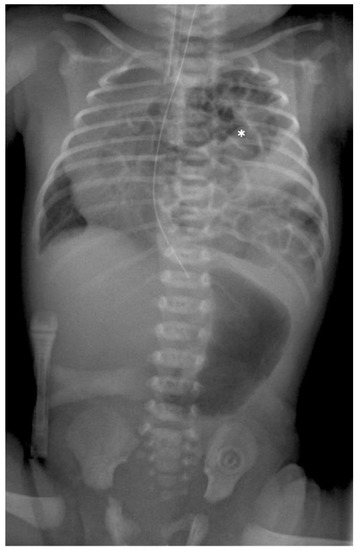

Preoperative Setting: After delivery, a plane X-ray image is taken at the intensive care unit (ICU) (see Figure 1). To rule out other associated anomalies, echocardiography and ultrasound of the brain and the abdominal organs are necessary. All patients were intubated between the first 2–4 h after birth in general to prevent abdominal distension and to avoid an additional compromise of the lung function. As soon as the patient is in a stable cardiorespiratory condition the surgical repair of the defect is performed. The patient is placed on the OR table in lateral decubitus position, the side of the defect upwards with an axillary roll underneath it, and the body is appropriately padded. The preoperative antiseptic routine is performed. Under complete relaxation by anesthesia three 3-mm trocars are placed in the standard location for CDH repair: one at the lower tip of the scapula for the camera, one in the frontal axillary line and one in the posterior. Insufflation pressures during operations are 3–6 mmHg with a flow of 1 L/min. Single lung ventilation is not needed. The herniated bowel is placed downwards into the abdomen and the size and nature of the defect are evaluated.

Figure 1. Preoperative radiograph of a left-sided CDH. The * indicates the intrathoracic bowel.